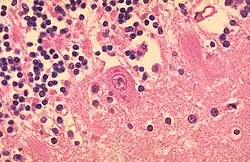

- LANGHANS-Riesenzellen - In Tuberkulosegranulomen, die Kerne sind hufeisenförmig angeordnet

- Käsige Nekrose - Bsp.: Tbc (Epitheloidzelliges Granulom mit Langhans-Riesenzellen und zentraler käsiger Nekrose)